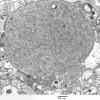

PERIPHERAL NEUROPATHY

5 AXONAL REGENERATION (3)